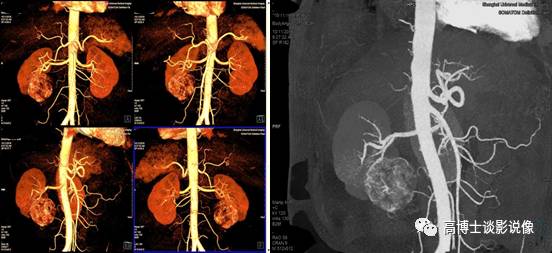

六、肾肿瘤血管术前评估

MIP重建显示肾脏肿瘤的供血类型、供血动脉、肿瘤血管团及有无动静脉瘘形成,显示动脉血管有无侵犯,显示肾静脉、下腔静脉内有无癌栓形成。去骨VR整体、直观显示双肾动脉整体解剖和变异血管起源、数目、走行等,判断其变异类型,显示有无异常血管团及狭窄、中断。为外科手术方案的制订、预防术中并发症及预测肿瘤的可切除率方面提供依据。